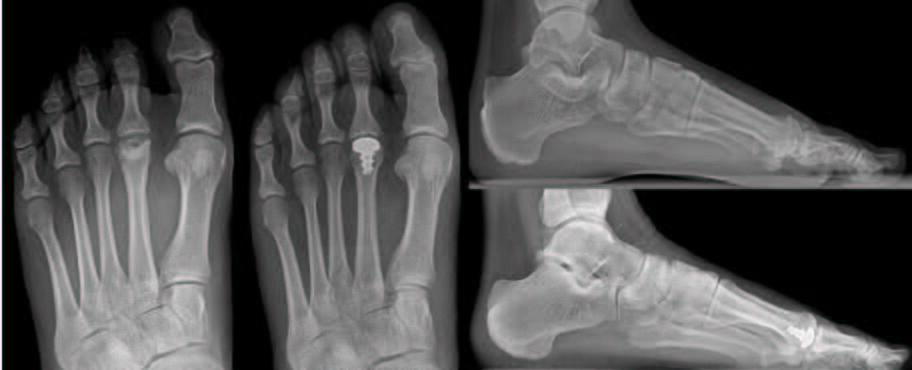

Metatarsal Head Resection. Pan-metatarsal head resection is a common procedure performed in late-stage rheumatoid arthritis; however, singular metatarsal head resection may introduce an increased risk of developing adjunctive pathologies when performed in isolation. This includes transfer metatarsalgia, shortening of the second digit, and even hallux valgus deformity. Adjunctive procedures such as a resection of the base of the proximal phalanx and interpositional arthroplasty following a metatarsal head resection may limit some of the complications seen with isolated metatarsal head resections.16 Singular metatarsal head resections are typically a last resort option in the senior author’s practice (see third photo set above).